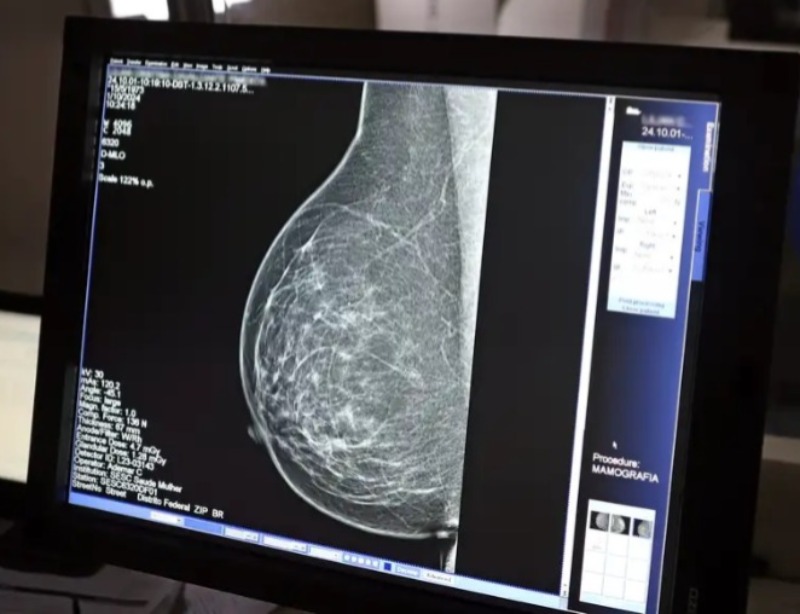

Dados do Painel Oncologia Brasil, analisados pelo Colégio Brasileiro de Radiologia e Diagnóstico por Imagem (CBR), indicam que mais de 108 mil mulheres com menos de 50 anos foram diagnosticadas com câncer de mama no Brasil no período entre 2018 e 2023 – uma média de uma em três mulheres diagnosticadas com a doença.

Para a entidade, os números reforçam a importância de ampliar o rastreamento do câncer de mama por meio da realização de mamografia em mulheres abaixo dos 50 anos e acima dos 70 anos, faixas etárias que não estão incluídas na recomendação padrão de exames preventivos no âmbito do Sistema Único de Saúde (SUS).

O levantamento mostra que, entre janeiro de 2018 e dezembro de 2023, o Brasil registrou mais de 319 mil diagnósticos de câncer de mama, sendo 157,4 mil em mulheres de 50 a 69 anos, faixa etária atualmente recomendada para o rastreamento.

Entre mulheres com idade entre 40 e 49 anos, foram registrados 71.204 casos de câncer de mama, enquanto 19.576 mulheres com idade entre 35 e 39 anos também receberam o diagnóstico da doença. Juntas, ambas as ocorrências representam 33% do total de casos diagnosticados no período.

Já entre mulheres acima de 70 anos, foram identificados 53.240 casos de câncer de mama.